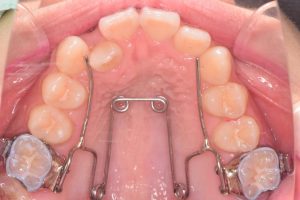

クワドヘリックスという装置で歯列の拡大を行い(1期治療)

上顎QH+ヘッドギア

4ヶ月

リンガルアーチ

2ヶ月

使用装置:クワドヘリックス、ヘッドギア